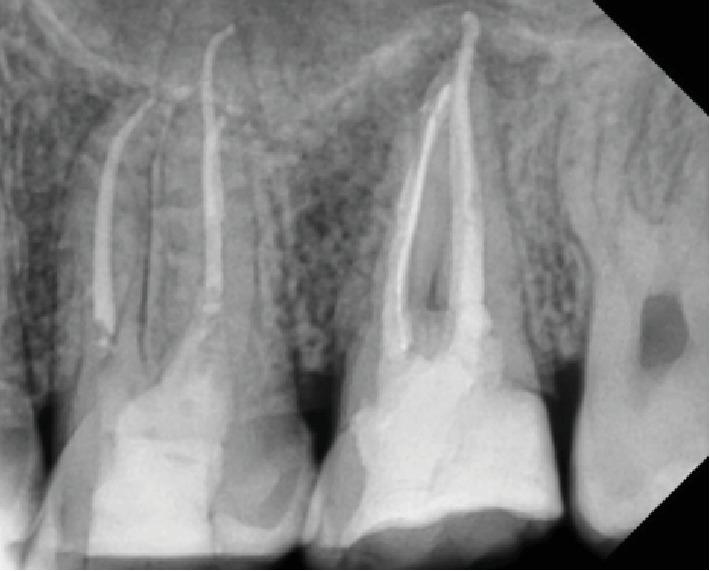

This case report illustrates the recovery of dizziness of a young healthy patient after root canal therapy of upper second molar. The patient developed dizziness and unbalanced walking four months ago. After cardiac, ENT, neurological, physiotherapy and medical investigations, his entire checkup showed no abnormalities. The patient visited a dental clinic for a routine checkup; after dental clinical and radiographical examination, a chronic abscess infection in an upper second molar region close to the sinus was diagnosed. Root canal therapy was performed that resulted in a disappearance of the dizziness and full recovery was achieved. Infected upper teeth with periapical lesion are associated with dizziness as a complication of odontogenic-related sinusitis. Dental and medical cooperation contributes to a better management diagnosis of the dizziness.

本病例报告阐述了一名年轻健康患者在上颌第二磨牙根管治疗后头晕症状的恢复情况。该患者四个月前出现头晕及行走不稳症状。在进行心脏、耳鼻喉、神经、物理治疗及医学检查后,其全面检查未发现异常。患者前往牙科诊所进行常规检查;经牙科临床及影像学检查,诊断出上颌第二磨牙区域靠近鼻窦处存在慢性脓肿感染。进行根管治疗后,头晕症状消失,患者完全康复。患有根尖周病变的感染上颌牙齿与作为牙源性鼻窦炎并发症的头晕有关。牙科与医学合作有助于更好地诊断和处理头晕症状。